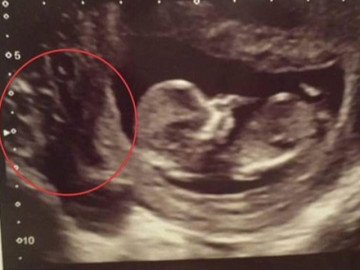

Mẹ bầu khóc ngất khi siêu âm thấy có nhiều " hố đen " ở nhau thai và quyết định bất ngờ

Do 2 lần mang thai đều rất suôn sẻ, cả hai con chào đời đều nặng hơn 3,5kg nên sản phụ nghĩ lần mang bầu này cũng vậy. Nhưng cô đã khóc nức nở khi nhìn hình ảnh siêu âm.